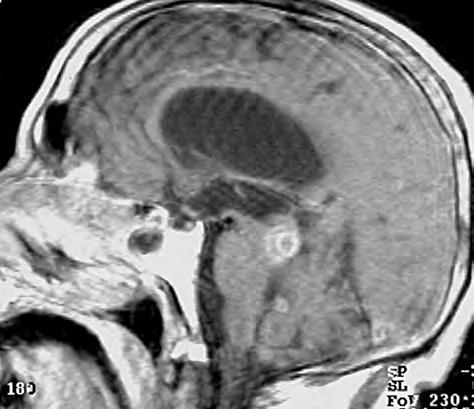

Obr. 1.1 Glioblastom, stav po kraniotomii, CT obraz po i.v. aplikaci kontrastní látky ukazuje heterogenní, expanzivně se chovající útvar s útlakem a přetlakem postranních komor a posunem středočárových struktur. Tvar je nepravidelný – na jednom řezu klamně působí jako multifokální. Rozpadlé centrum je ohraničeno prstenčitou zónou zvýšeného enhancement (hyperdenzity) po aplikaci k.l. i.v. představující oblast nádoru s porušenou hematoencefalickou bariérou –šipka bílá. Okolí útvaru je ovládnuto hypodenzním perifokálním edémem, který však obsahuje nádorové buňky – šipka čárkovaná. Hranice edému představuje prakticky hranici nádoru.

CT nebo MR vyšetření je podstatné vědět, že vnativním zobrazení nemusí být tumor vždy zřetelný, proto je nutné provést vyšetření spoužitím kontrastních látek. Výsledek zobrazovacího vyšetření může svelmi vysokou pravděpodobností informovat opřítomnosti maligního expanzivního ložiska viz obr. 1.1., 1.2., 1.3. Takovýto nález je dostatečnou indikací koperačnímu zákroku. Vdětském věku je možné provést ultrasonografické vyšetření mozku.

1.2 Glioblastom – ve srovnání s CT poskytuje MR vyšetření více detailů jak o struktuře nádoru, tak i o jeho prostorovém rozsahu, umístění a vztahu k mozkovým strukturám. Za příklad slouží parasagitální řez v T1 váženém čase po aplikaci kontrastní látky i.v.

Obr. 1.3 CT pokročilého astrocytomu III.stupně, který je nápadný rozsahem své velikosti, expanzivním chováním a kolaterálním edémem.

Informace, které lze získat odborným hodnocením MR či CT zobrazení mozku

Nález multiformního glioblastomu se při CT vyšetření zobrazuje jako hypodenzní ložisko s často vyjádřeným mass-efektem. Po nitrožilním podání kontrastní látky se uvíce než 90%nemocných zobrazuje hyperdenzní prstenec, tzv. ring sign Tento nález není typický jen pro glioblastom, ale je možno se sním setkat iumozkového abscesu. Podobně jako glioblastom může hypodenzní ložisko vCT obraze vytvořit rovněž metastatický nádor nebo infarkt mozku. Edém obklopující glioblastom je rozsáhlý amá nepravidelný prstovitý charakter. Po podání kontrastní látky se nasycení (enhancement) nevytvoří u60 %nízkostupňových astrocytomů, 30 %anaplastických astrocytomů, ale pouze

u6,5%glioblastomů. Platí, že čím vyšší je malignita, tím větší je imass-efekt.

Nový pohled na předoperační stanovení histologické klasifikace gliomů přineslo zavedení MR. Astrocytomy typu low-grade se vT2 váženém zobrazení znázorňují jako relativně homogenní léze vysoké intenzity. Ugliomů typu high-grade se znázorňuje nehomogenně hyperintenzní centrum ohraničené lemem méně zvýšené intenzity. Periferně leží zóna tvořící hyperintenzní široký lem sprstovitými výběžky. Podání gadolinia zpravidla vede kvytvoření enhancement. Vpodstatě platí, že heterogenita signálu spolu svýrazným mass-efektem odpovídá vyššímu gradingu.